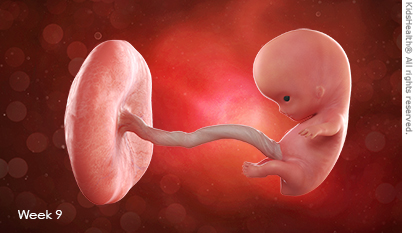

My baby at 9 weeks old 2025

My baby at 9 weeks old 2025, 9 Weeks Pregnant Week by week guide NHS 2025

My baby at 9 weeks old 2025

9 Weeks Pregnant Week by week guide NHS

9 Weeks Pregnant Baby Development Symptoms and More

9 Weeks Pregnant Your Symptoms Having an Ultrasound

Baby and You at 9 Weeks Pregnant Symptoms and Development

Week 9 for Parents Nemours KidsHealth

The Guardian is wrong this is what a 9 week old unborn baby looks

Product Item: My baby at 9 weeks old 2025